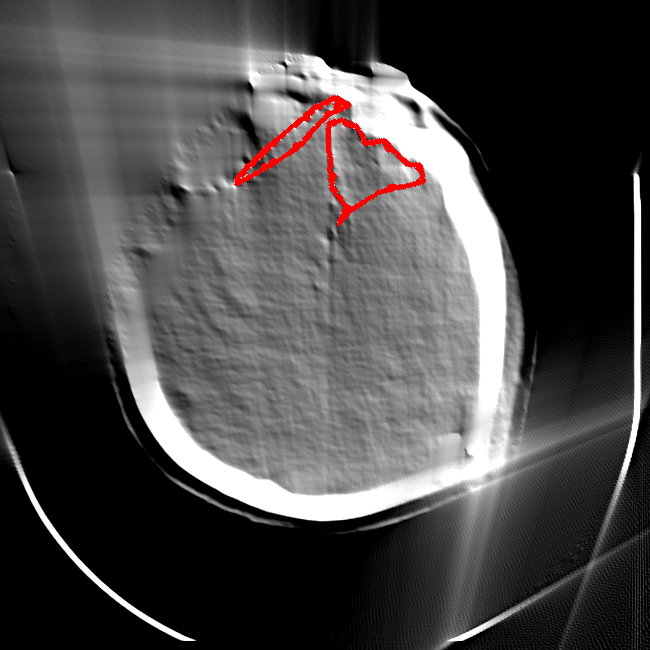

Limited Angle

CT GMAIMMbench Disease Diagnosis

Limited Angle - L0 (Original)

L0 (Original)

Limited Angle - L1 (Moderate)

L1 (Moderate)

Limited Angle - L2 (Severe)

L2 (Severe)

Question

This is a CT image. Which of the following options is the most appropriate to demonstrate the marked area?

A brain hemorrhage B barrett's esophagus C thyroid nodule D retinal hard exudates

Ground Truth: A. brain hemorrhage